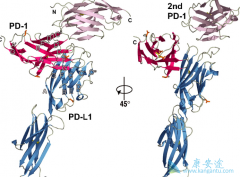

PD-1抑制剂 纳武单抗 (Nivolumab)与CTLA4抑制剂伊匹单抗,可通过激活免疫系统以对抗癌症。既往研究提示两种单抗分别对肾细胞癌有效,并且在其他肿瘤治疗中两者联用比单用有效。舒尼替尼是血管内皮生长因子受体酪氨酸激酶抑制剂,为晚期肾细胞癌的一线 ...

近几年,癌症治疗发生了天翻地覆的变化。以 PD-1抑制剂 为代表的癌症免疫疗法,正在逐渐成为癌症治疗的新希望。PD-1抑制剂在多个癌症治疗的临床实验中,都展现除了超过传统癌症疗法如化疗的疗效,是目前癌症治疗的领先治疗方案。 截止到目前,PD-1抗 ...